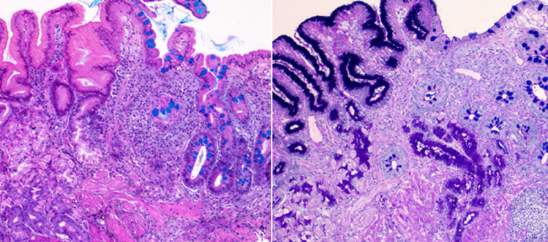

장상피화생은 위 점막이 장 점막처럼 바뀌는 현상입니다. 위 점막은 본래 산성 환경에서 잘 버틸 수 있도록 구성되어 있지만, 오랜 기간 위염이나 헬리코박터균 등에 의해 자극을 받을 경우 장 세포처럼 변형되기도 합니다. 이는 위의 방어기능이 약해졌다는 신호로 볼 수 있지요.

하지만 중요한 건 그 '가능성'이 존재한다는 것입니다. 저도 검색을 통해 알게 되었는데, 특히 장상피화생이 '광범위하거나', '불완전형'일 경우 위험도가 올라간다는 연구 결과들이 있었습니다. 물론 이것이 모든 사람에게 동일하게 적용되는 것은 아니며, 생활습관과 유전, 감염 상태 등 복합적인 요소에 의해 결정됩니다.